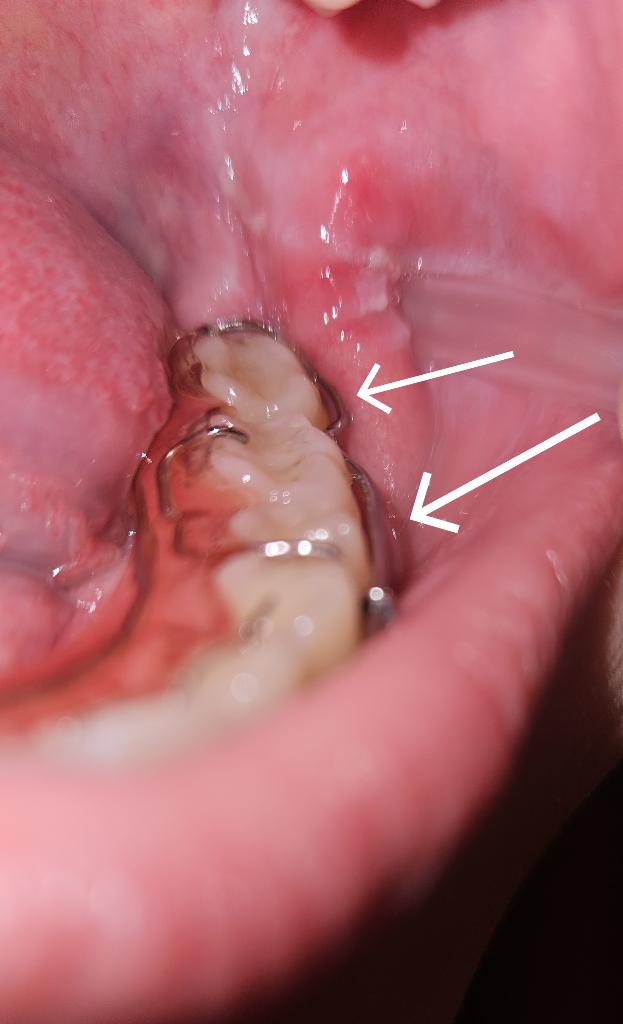

해당 부위는 유지 장치에 치아를 잡아주는 클래스프라고 하는 장치입니다 원래 형태가 약간 떠 있을 수 있도록 되어 있기 때문에 해당 부위로 치아가 이동하거나 장치훈의 변화가 생기진 않습니다

유지장치 구조상 해당 부위는 원래 전체가 다 닿지는 않습니다 adam's clasp를 구글 등에서 사진검색해보시기 바랍니다